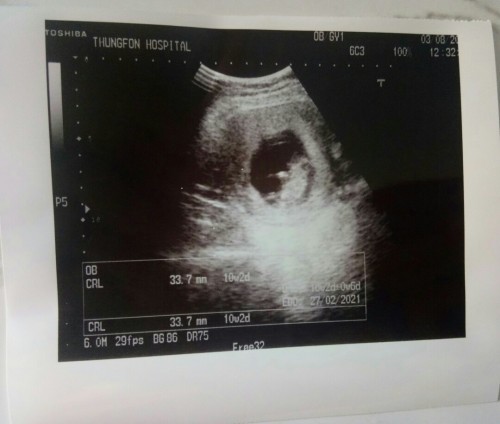

27กุมภาจ้าตอนนี้ได้12w